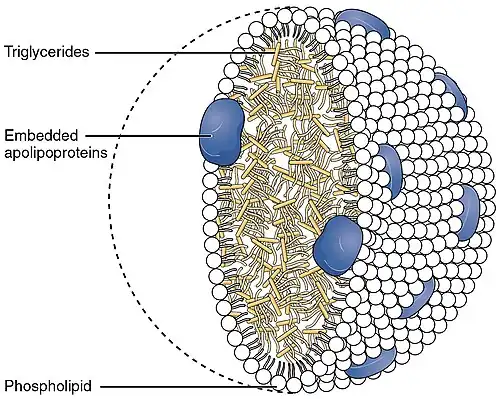

Apolipoprotein AI is the major protein component of high density lipoprotein (HDL) particles in plasma.[10]

Chylomicrons secreted from the intestinal enterocyte also contain Apo-AI, but it is quickly transferred to HDL in the bloodstream.[11]

The protein, as a component of HDL particles, enables efflux of fat molecules by accepting fats from within cells (including macrophages within the walls of arteries which have become overloaded with ingested fats from oxidized low-density lipoprotein (LDL) particles) for transport (in the water outside cells) elsewhere, including back to LDL particles or to the liver for excretion.

It is a cofactor for lecithin–cholesterol acyltransferase (LCAT) which is responsible for the formation of most plasma cholesteryl esters. Apolipoprotein AI has also been isolated as a prostacyclin (PGI2) stabilizing factor, and thus may have an anticlotting effect.[12] Defects in the gene encoding it are associated with HDL deficiencies, including Tangier disease, and with systemic non-neuropathic amyloidosis.[7]